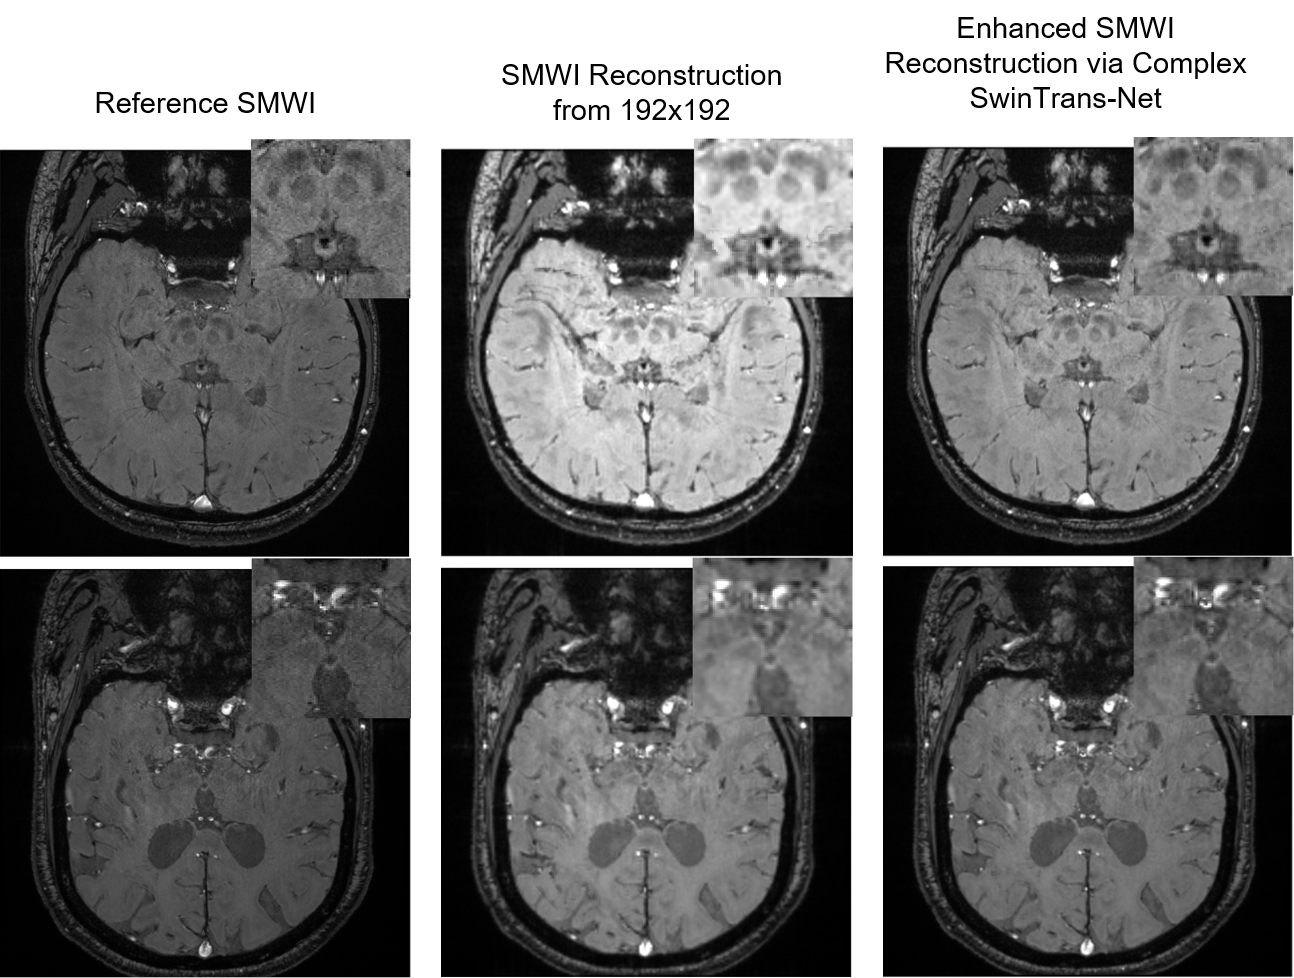

We conducted quantitative and qualitative evaluations on the 64 test scans. For k-space data of 256×\times256, the proposed method achieved an MSE of 0.064 ±\pm 0.050, MAE of 1.66 ±\pm 0.635, and SSIM of 91.16 ±\pm 2.89. For k-space data of 192×\times192, we achieved an MSE of 0.079 ±\pm 0.075, MAE of 2.07 ±\pm 1.00, and SSIM of 89.74 ±\pm 2.53. Figures 3 and 4 display the qualitative results, demonstrating that our method preserves essential diagnostic information in the reconstructed SMWI images.

Refer to caption

Figure 3: Demonstration of visual results obtained from low resolution data (i.e., 192×\times192) by employing proposed complex Swin Transformer Network.